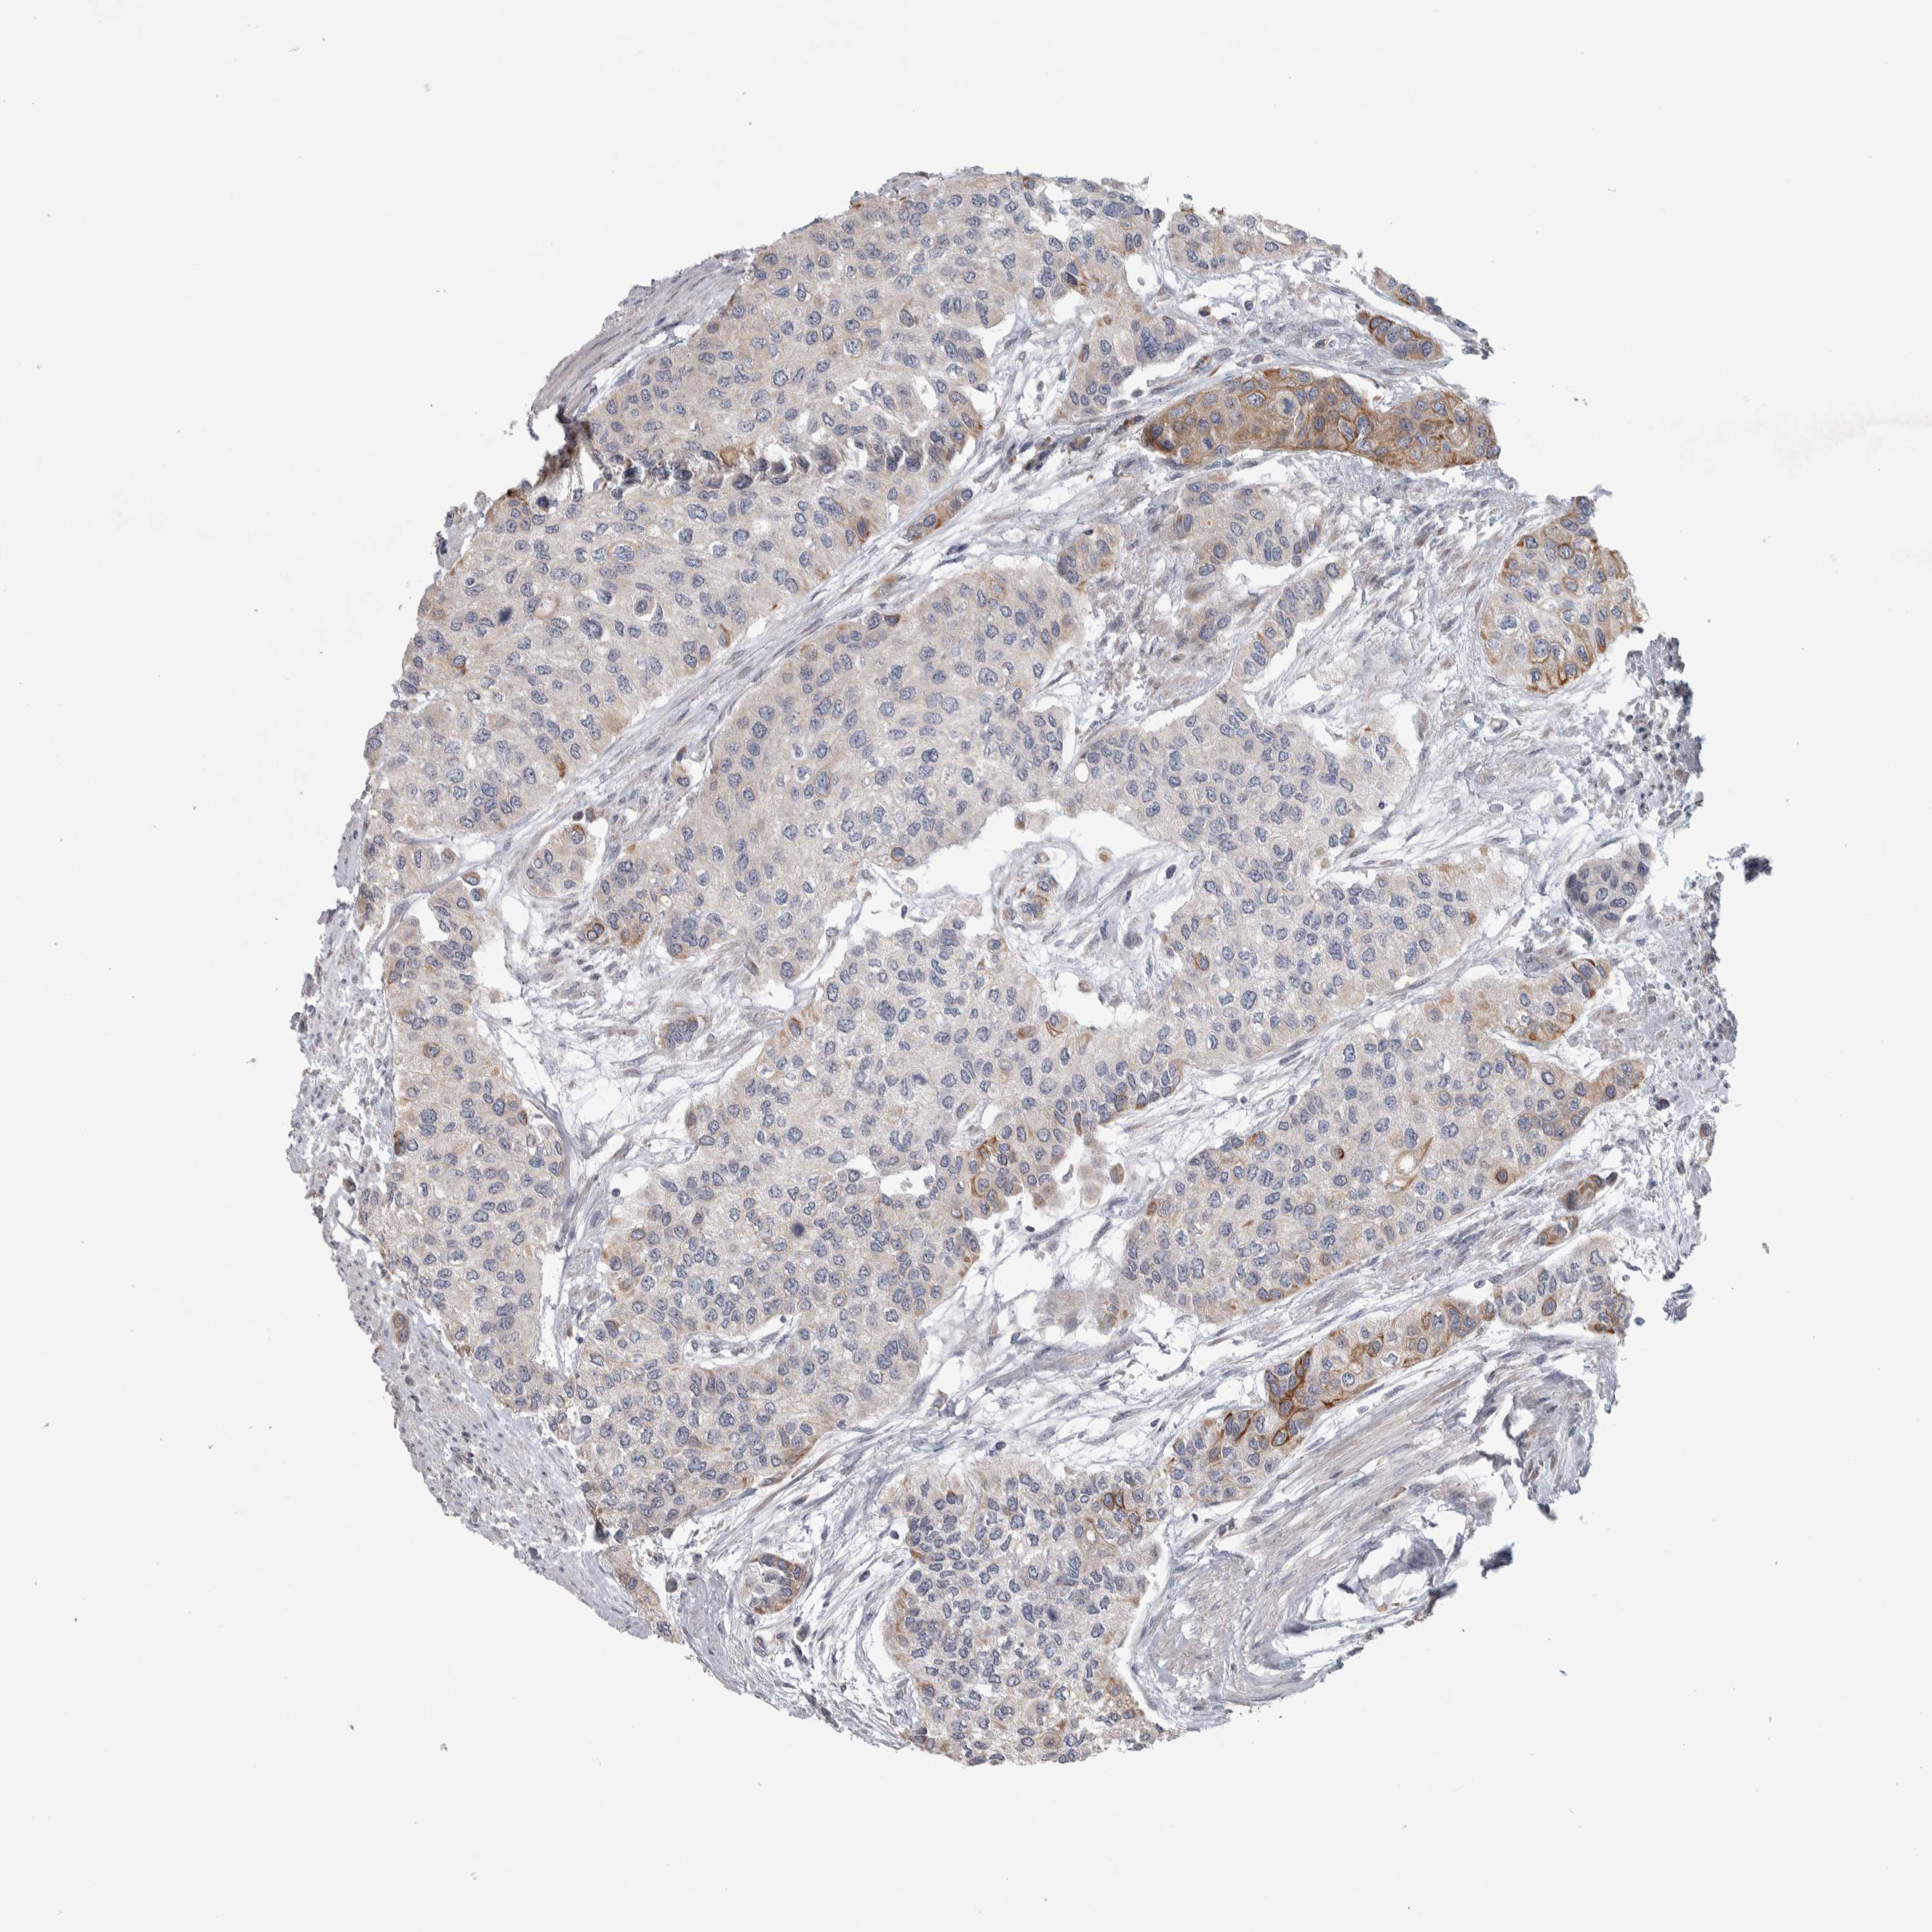

UROTHELIAL CANCER - Protein expressioni

A mouse-over function shows sample information and annotation data. Click on an image to view it in a full screen mode. Samples can be filtered based on level of antibody staining by selecting one or several of the following categories: high, medium, low and not detected. The assay and annotation is described here.

Note that samples used for immunohistochemistry by the Human Protein Atlas do not correspond to samples in the TCGA dataset.

Antibody stainingi

Antibody staining in the annotated cell types in the current human tissue is reported as not detected, low, medium, or high, based on conventional immunohistochemistry profiling in selected tissues. This score is based on the combination of the staining intensity and fraction of stained cells.

Each image is clickable and will lead to virtual microscopy that enables deeper exploration of all samples and also displays staining intensity scores, fraction scores and subcellular localization as well as patient and tissue information for each sample.

Antibody HPA023303

Staining

High

Medium

Low

Not detected

Intensity

Strong

Moderate

Weak

Negative

Quantity

>75%

75%-25%

<25%

None

Location

Nuclear

Cytoplasmic/membranous

Cytoplasmic/membranous,nuclear

Urothelial carcinoma, Low grade

Urothelial carcinoma, High grade